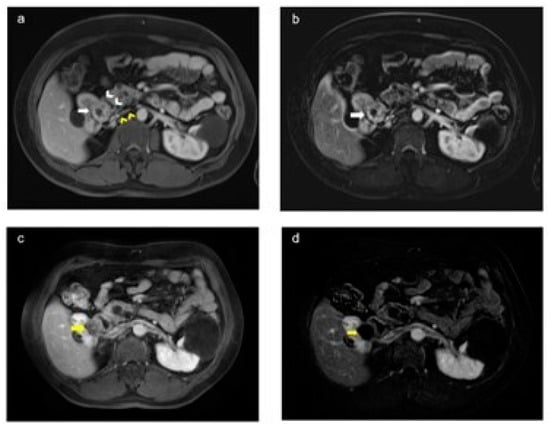

2.1. Percutaneous Microwave Ablation Therapy

2.3. Laparoscopic Ultrasound-Guided Percutaneous Microwave Ablation Therapy